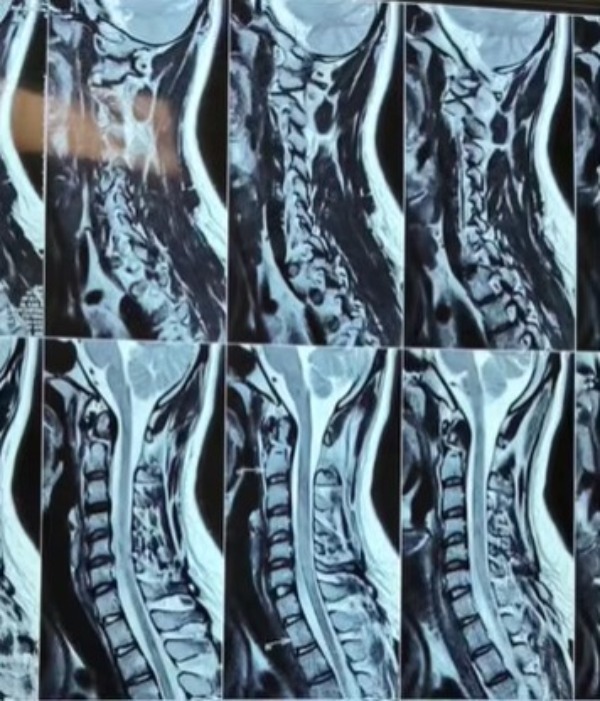

Dr Amit Aiwale-Best Neurosurgeon in Thane Dr Amit Aiwale, Solaris Super Speciality Hospital, Service Road, Ghodbunder Road, Next to AP Shah Institute of Technology, Kasarvadavali, Thane West, Thane 400615 +918048126686 dramitaiwale@gmail.com